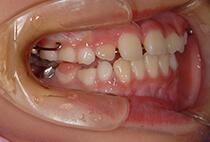

5歳6ヶ月、受け口が気になり、お母様と一緒にご来院。

「幼稚園の間に治療スタートしたい」「小学校入学時には装置に慣れた状態でいたい」とのご希望で、矯正治療をスタートしました。

治療は、急速拡大+前方牽引装置から。

1ヶ月で骨格バランスが大きく改善しました。

小学1年生の7ヶ月後には、さらにバランスの整った噛み合わせに。

成長に合わせて3回の急速拡大を行い、夜間のマウスピースとお口の機能訓練で成長をサポート。

小学生を正常なバランスで過ごすことができました。

中学校入学と同時にマウスピースを卒業し、今後は予防管理へ移行予定です。

「早めに始めてよかった」と喜んでいらっしゃいます。